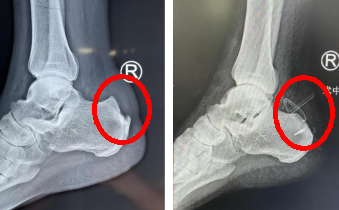

接診的趙亮主治醫(yī)師經(jīng)過(guò)仔細(xì)查體及x光片檢查,診斷孟師傅患有跟腱末端病、Haglund綜合征,是由于Haglund畸形導(dǎo)致跟腱及周?chē)也∽?,引起的足部后跟痛,早期可以選擇保守治療,但發(fā)展到孟師傅這種程度就需要手術(shù)干預(yù)了。

術(shù)前

術(shù)前術(shù)后x光對(duì)比